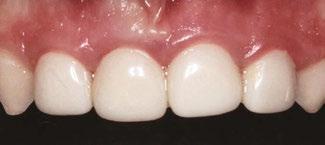

around these clinical sites. His anterior zirconia crowns showed healthy gingival margins with little-to-no plaque accumulations. This positive clinical finding is from the highly polished nature and biocompatibility of pediatric zirconia crowns. These restoration features limit plaque accumulations on the restoration and along the marginal gingiva, providing a localized positive aspect directly related to the choice of restorative material (Figure 2).

Case 2

A 3-year-old female presented with pulpal necrosis and abscess on #E and pulpal necrosis on #F. Extraction therapy or pulpectomy was offered. The family was highly motivated to retain #E and #F. The pulpectomy was performed with 0.02 K-Flex hand files, 3% NaOCl with a lateral vented needle, obturated with Vitapex (Neo Dental International Inc., Federal Way, Washington), a premixed paste of calcium hydroxide and iodoform. The access was filled with a HVGIC sealing the pulp therapy and increasing the clinical success by minimizing the potential for bacterial contamination. NuSmile ZR anterior crowns were selected as offering a full-coverage, esthetic, cemented restoration with no polymerization shrinkage when compared to a composite restoration. Crowns were cemented with NuSmile® BioCem (NuSmile, Houston, Texas). This is clinically beneficial as the provider would want to cement a restoration that provides limited microleakage minimizing the potential for bacterial contamination.15-17 At 6-month follow up, lesion healing had occurred with healthy gingival margins and no plaque accumulations (Figure 3).

Figure 3: NuSmile® ZR Crowns were selected as a cementable full coverage restoration. At 6-month recall, apical tissues were healed with excellent gingival health Figure 4: SMART style restorations that were definitively restored with NuSmile® ZR Crowns as an esthetic option to cover SDF staining